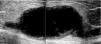

Clinical caseThe patient is a 72-year-old female, with no positive background of chronic degenerative diseases or of any other type, and a negative history of smoking. The patient presented an increase in volume of the right pelvic limb 10 days after undergoing surgery to correct a direct inguinal hernia using the Bassini–Shouldice technique. The subject pointed out that for over 40 years she presented a soft tumor of approximately 10cm, located in the middle third of the medial part of the right thigh 22cm from the inguinal fold. The tumor was soft, palpable and painless with a variation in volume depending on the position and did not cause any discomfort. Subsequent to the hernioplasty the patient began noticing that the tumor hardened and caused pain, along with redness and an increase in local temperature, consequently the physician diagnosed a cellulitis and prescribed antibiotic therapy. The symptomatology did not improve with the prescribed treatment and now presented an increase in volume of the entire pelvic member. She was therefore referred to our service. During the examination a difference of 5cm in volume between both pelvic members was observed, noticing a hard, non-mobile, painful lump of 9×6cm. The rest of the examination was normal. A vascular ultrasound was performed, showing a non-palpable, anechoic growth, connected to the great saphenous vein, of 9×5cm (Fig. 1) without the presence of venous reflex neither in the great saphenous nor in the saphenofemoral junction. Moreover, a posterior tibial vein thrombosis was detected. With a great saphenous vein aneurysm diagnosis, the patient was transferred to surgery where an aneurysmectomy and SFJ ligation were performed (Figs. 2 and 3).

The diagnosis can be made by the clinical history and physical examination in most cases, but it is usually confirmed by image studies. Within image studies, vascular ultrasound is the method of choice for the study of VAs.25 In the ultrasound, VAs are presented as an anechoic cystic structure, with well-defined walls, which can be secular or fusiform and with a low flow volume; also, they provide us with information on vascular connections, the existence of thrombosis, or if there is an associated arteriovenous fistula or any other pathologies,26 in addition to guiding the therapeutic approach. The CAT scan, the MRI and the phlebography are studies which can be performed in case of diagnostic doubt or when more exact information is required (size, extension, associated lesions and vascular origin).27 Clinical history and examination are the basis for reaching any diagnosis, but in the case of venous problems, vascular ultrasound evaluation is fundamental to reaching a correct diagnosis, and thus choosing the proper treatment. It is only in case of doubt, where further imaging studies are required. In the differential diagnosis, we must consider varicose veins, soft tissue tumors, hygromas, hemangiomas and, depending on location, inguinal hernias. Vascular aneurysm complications are: thrombophlebitis, deep venous thrombosis, pulmonary embolism and bleeding caused by rupture.